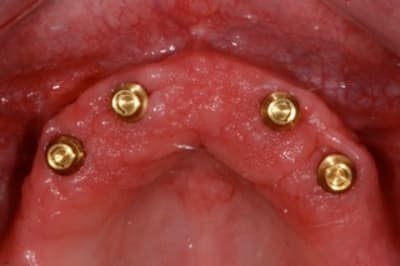

complet haut amovible sur deux barres (donc 4 implants en haut) ou sur 4 locators (y en a qui ont déjà fait ?)